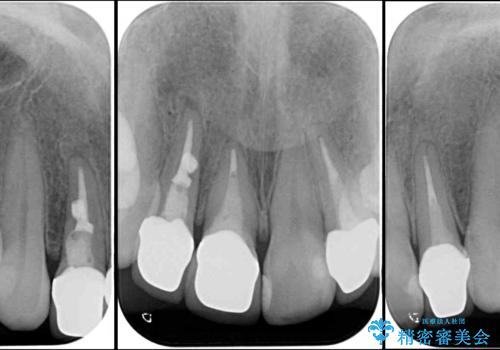

- 以前治療した前歯のクラウンの色が気になるとのことで来院された患者様です。

3歯別々に治療したクラウンは、どれも未治療の前歯を異なる色調で、口元が縞模様の印象でした。

更に、土台やフレームの金属色により、歯肉ラインが黒ずんでしまっていました。

必要な歯には根管治療を行い、金属を使わない土台を植立した上で、オールセラミッククラウンにて補綴することとしました。